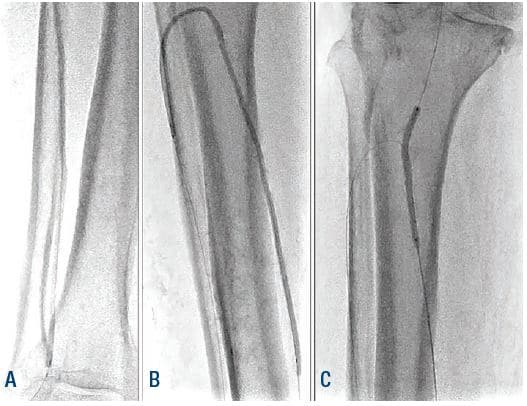

Anticipating a high risk of complications related to transfemoral access, we decided to proceed with TAMI approach with transradial guidance. A 4- to 5-Fr Glidesheath Slender (GSS) (Terumo Medical) was inserted in the right radial artery for visualization of the proximal vessels. We placed a 2.9-Fr Cook pedal (Cook Medical) sheath in the ATA and advanced a 0.018-inch CXI (Cook Medical) support catheter over a 0.018-inch Command ST (Abbott Vascular) wire. The CXI catheter and wire were advanced through the course of the ATA intraluminally except for the ostium of the ATA where the wire entered a subintimal space. Thereafter, we gained access in the right PT with a 4- to 5-Fr GSS sheath to serve as an antegrade access to cross the ATA CTO (Figure 2). A 0.018-inch CXI support catheter was telescoped within a 4-Fr Berenstein (Boston Scientific) catheter with a 0.018-inch Command wire advanced into the proximal ATA (Figure 3). The antegrade equipment was advanced into the distal ATA. The retrograde CXI catheter was pulled back in the distal AT where the antegrade wire was inserted for externalization. Subsequently the antegrade CXI catheter was externalized through the retrograde 2.9-Fr sheath placed in the distal ATA (Figure 4). The 0.018-inch Command wire was exchanged for a 0.014-inch ViperWire (Cardiovascular Systems, Inc.) guidewire to perform therectomy using a 1.5 mm Classic CSI Diamondback 360 catheter in the PTA, TPT, and ATA (Figure 5). Thereafter, based on extra vascular ultrasound (EVUS) measurements, we performed balloon angioplasty of proximal DPA, ATA, and PTA with a 3.5-x 300-mm balloon (Ultraverse BD Bard), and TPT with a 4.0- x 60-mm Lutonix DCB (BD Bard) with an excellent result (Figure 6).